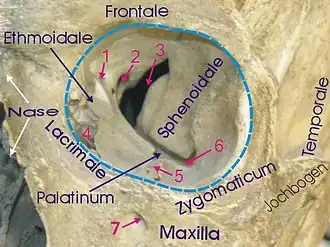

yellow = frontal bone

green = lacrimal bone

brown = ethmoid bone

blue = zygomatic bone

purple = maxillary bone

aqua = palatine bone

red = sphenoid bone

teal = nasal bone (illustrated but not part of the orbit)

The bony walls of the orbital canal in humans do not derive from a single bone, but a mosaic of seven embryologically distinct structures: the zygomatic bone laterally, the sphenoid bone, with its lesser wing forming the optic canal and its greater wing forming the lateral posterior portion of the bony orbital process, the maxillary bone inferiorly and medially which, along with the lacrimal and ethmoid bones, forms the medial wall of the orbital canal. The ethmoid air cells are extremely thin, and form a structure known as the lamina papyracea, the most delicate bony structure in the skull, and one of the most commonly fractured bones in orbital trauma. The lacrimal bone also contains the nasolacrimal duct. The superior bony margin of the orbital rim, otherwise known as the orbital process, is formed by the frontal bone.[8]

The roof (superior wall) is formed primarily by the orbital plate frontal bone, and also the lesser wing of sphenoid near the apex of the orbit. The orbital surface presents medially by trochlear fovea and laterally by lacrimal fossa.[9]

The floor (inferior wall) is formed by the orbital surface of maxilla, the orbital surface of zygomatic bone and the minute orbital process of palatine bone. Medially, near the orbital margin, is located the groove for nasolacrimal duct. Near the middle of the floor, located infraorbital groove, which leads to the infraorbital foramen. The floor is separated from the lateral wall by inferior orbital fissure, which connects the orbit to pterygopalatine and infratemporal fossa.

The medial wall is formed primarily by the orbital plate of ethmoid, as well as contributions from the frontal process of maxilla, the lacrimal bone, and a small part of the body of the sphenoid. It is the thinnest wall of the orbit, evidenced by pneumatized ethmoidal cells.[9]

The lateral wall is formed by the frontal process of zygomatic and more posteriorly by the orbital plate of the greater wing of sphenoid. The bones meet at the zygomaticosphenoid suture. The lateral wall is the thickest wall of the orbit, important because it is the most exposed surface, highly vulnerable to blunt force trauma.

Orbita

Orbita -